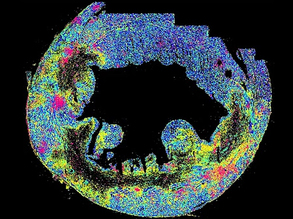

Mammary Map